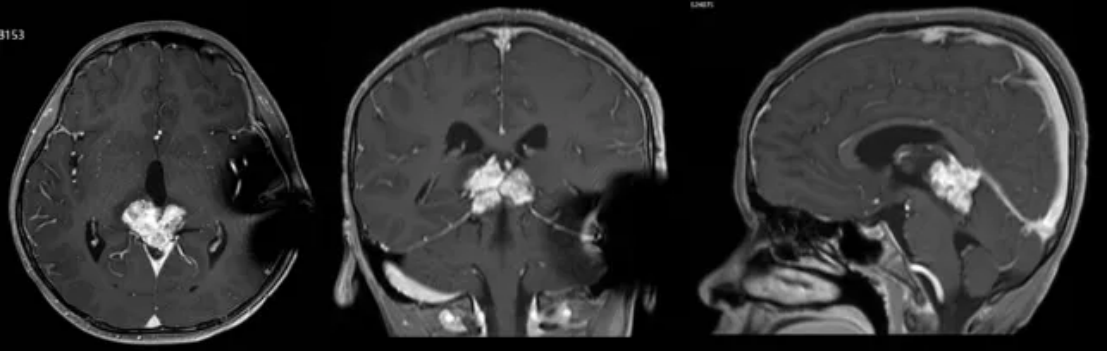

颅脑MRI+C检查提示:1.松果体区巨大占位;2.梗阻性脑积水(图1)。

图1 头部MR检查